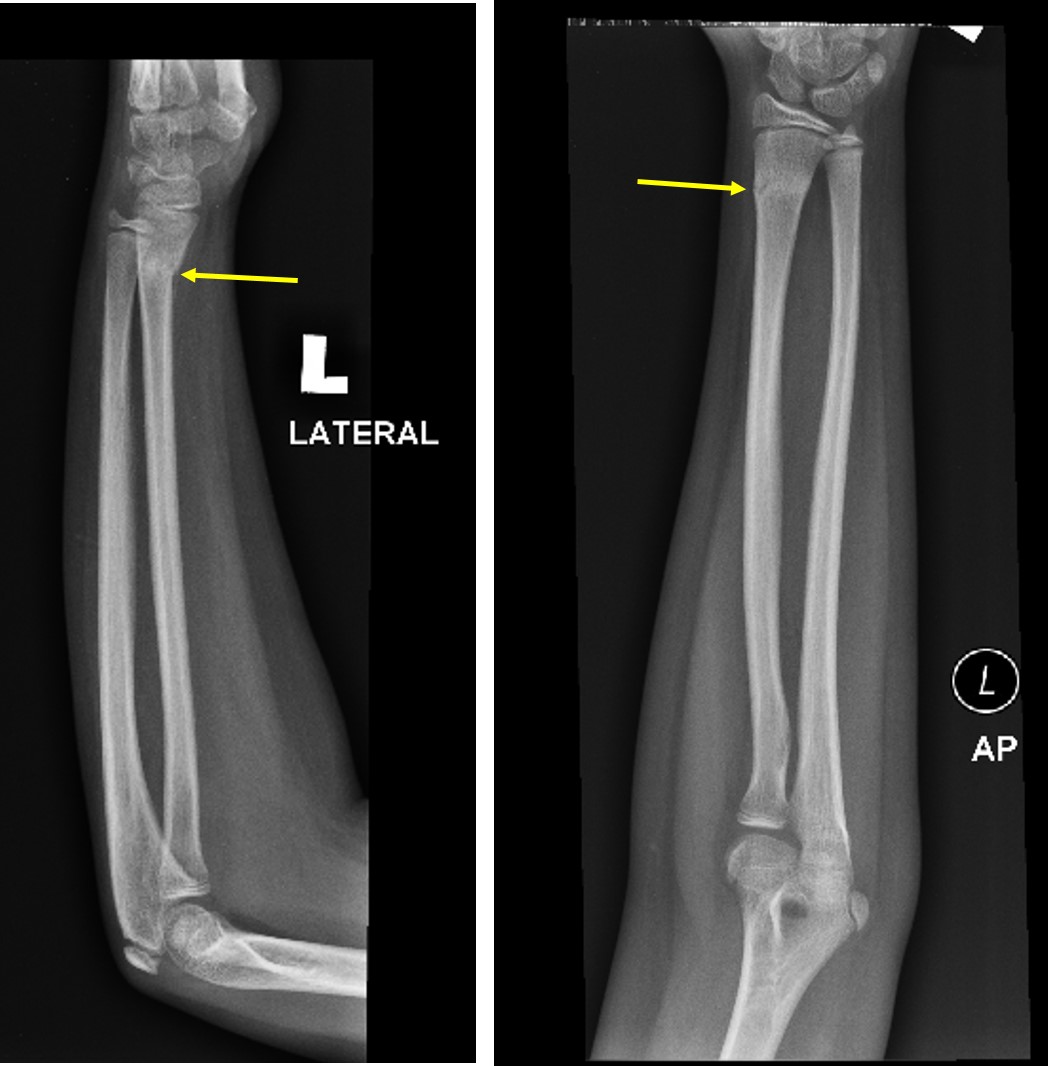

AP Radiograph Of Torus Fracture | Download Scientific Diagram

AP radiograph of torus fracture | Download Scientific Diagram www.researchgate.net

Torus Fracture - Diagnosed With Ultrasound – International Emergency

Torus Fracture - Diagnosed with ultrasound – International Emergency iem-student.org